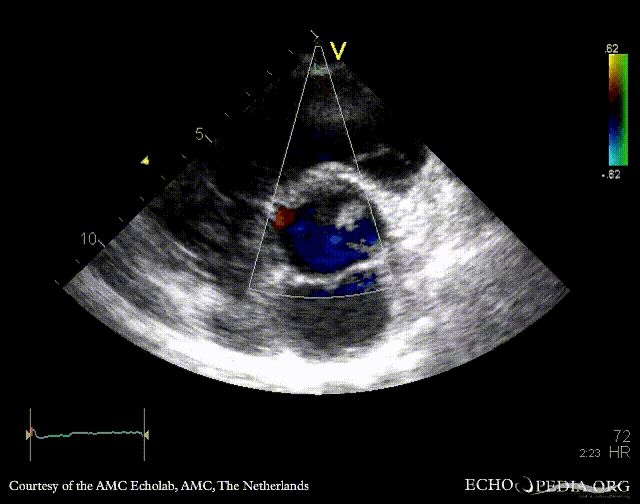

E00337.gif E00338.gif

PSAX: bicuspid aortic valve with raphe PSAX: Color Doppler, mild aortic regurgitation